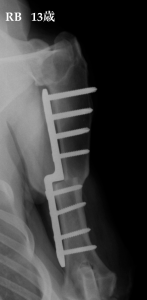

写真 左 遠位尺骨骨切術 右 近位尺骨骨切術 年齢や状態により骨切部位を変えて行われます。手術した足は、翌日から使用する事ができます。

写真 8ヶ月齢のバーニーズマウンテンドッグ。左 通常は、既に癒合していなければいけない肘の骨(肘突起)↓が癒合していません。右 スクリューにて肘突起を固定して安定させています。